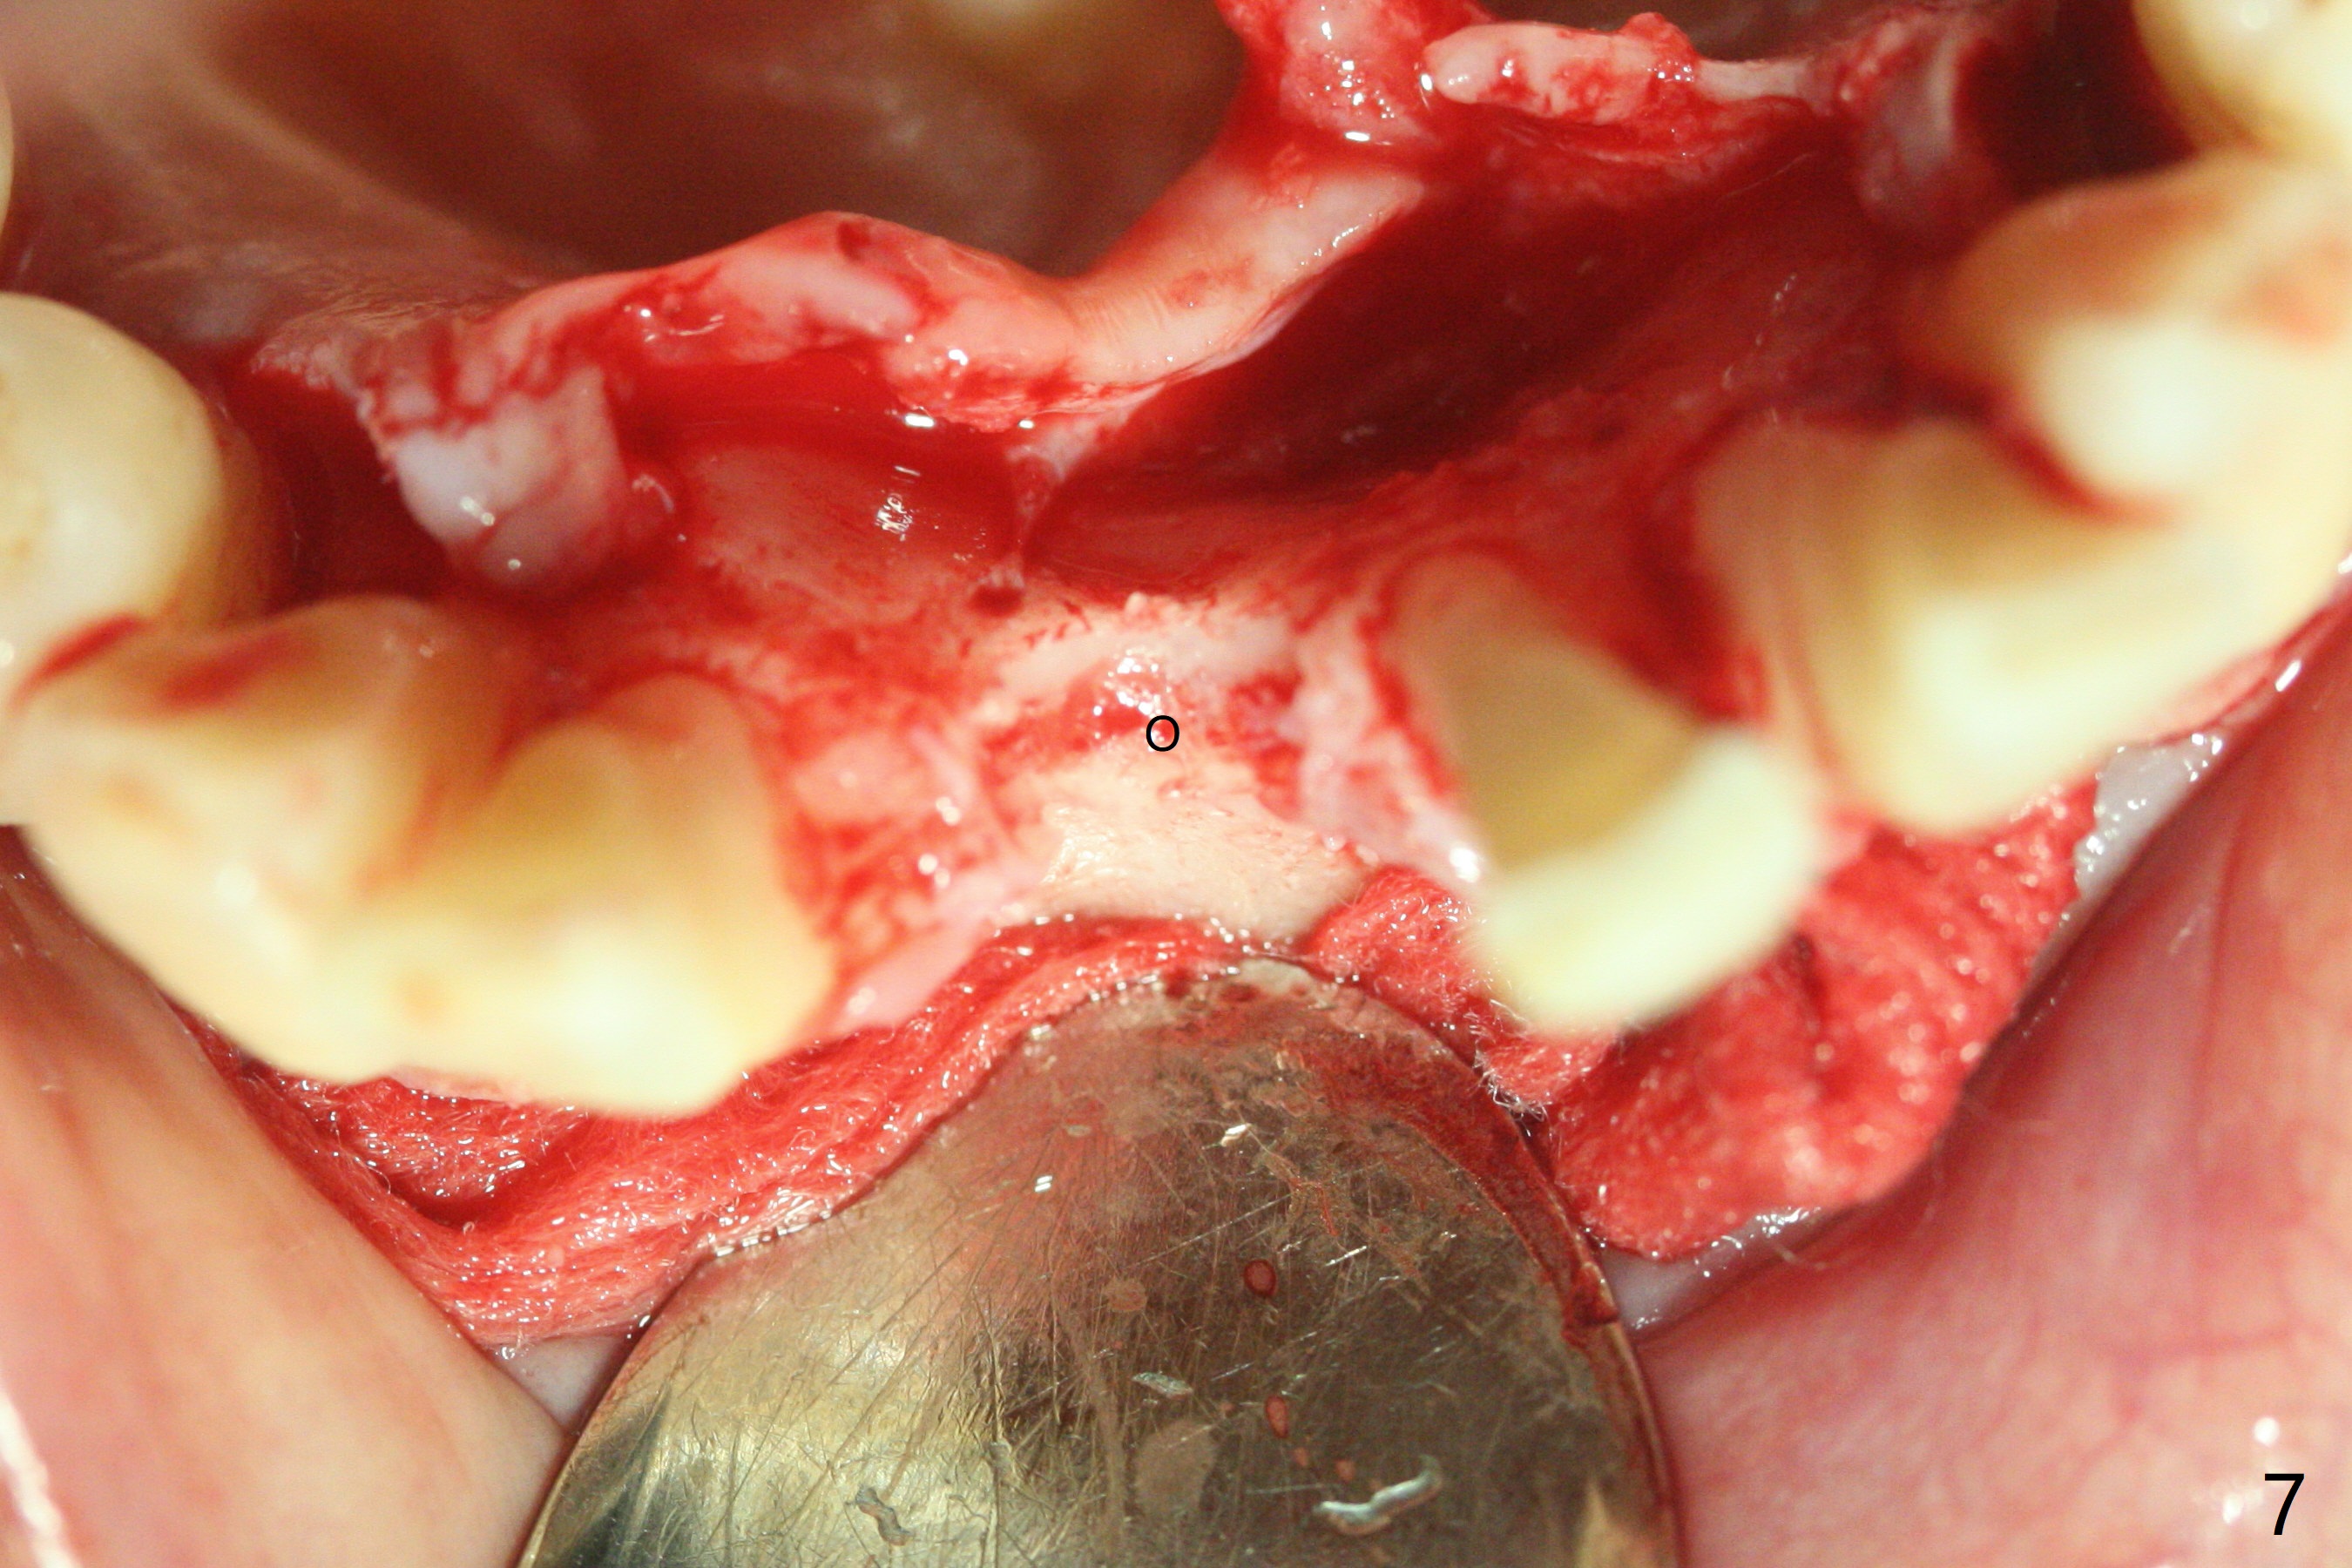

56岁女十分恐惧治疗,缺失右下1,其余切牙由于骨质吸收颊侧移位(图一:1,2),但是她不愿意拔除,同意右下1种植,牙周骨手术,植骨;植体整合后作为支抗,矫正移位下门牙。为了防止忘记舌侧瓣分离,先做舌侧切口(图二),然后颊侧瓣松弛分离(图三),包括使用前牙隧道刀(图四)切断颊侧骨膜,松弛到颊侧瓣能向舌侧牵拉3-4毫米(图五),舌侧瓣骨膜下广泛,深部分离(好像不能切断骨膜,图六),放置导板,磨平狭窄的牙槽嵴(图七:O(osteotomy)),植入2.5x12(4)毫米一段式植体(图八:故意舌侧植入,以便以后矫正),在颊侧骨板打多个出血洞(图八:箭头),然后把在平的器皿上形成的粘性骨板(sticky bone,图九),放置于植体和移位切牙周围(图十),接着使用消毒过的橡皮障punch(图十一(纸头相当于PRF膜;事先给助手示范))在三个PRF膜(图十二)打洞,套在植体和门牙上(图十三: 箭头),防止膜(图十四)和骨块(图十五,十六:*)移位,最后还必须使用最原始方法牙周敷料保护伤口(图十七)。术后9天,舌侧牙周敷料脱落,伤口稍微裂开(图十八)。术后18天撤除敷料,伤口裂开处有新鲜肉芽组织生长(图十九(*:下面是填入的骨粉,将是增宽的牙槽嵴(如果你是乐观主义者)),二十)。病人十分感激我们帮助她度过难关。她的确有sleep apnea,否定tongue thrust。术后三个月植体周围没有明显骨质吸收(图二十一至二十三),左下1,2轻度反合(图二十四),植体周围软组织健康(图二十五),5-5安置矫正器(图二十六,二十七,12 niti)。一周后下切牙向舌侧移动(图二十八),左下1,2反合纠正(图二十九)。再一周变化不大(图三十),植牙圈有些松动,两周后将重做临时牙冠,槽往舌侧移动。结果病人提前回来,植牙槽舌侧移位。一周后右下2不适(图三十一),尝试近中牵引(图三十二)。